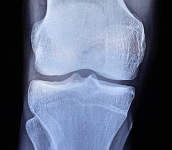

2. 진단 기준 – T-score 수치로 구체적으로 확인해요

골밀도 검사의 T-score를 기준으로 골 상태를 판별할 수 있어요.